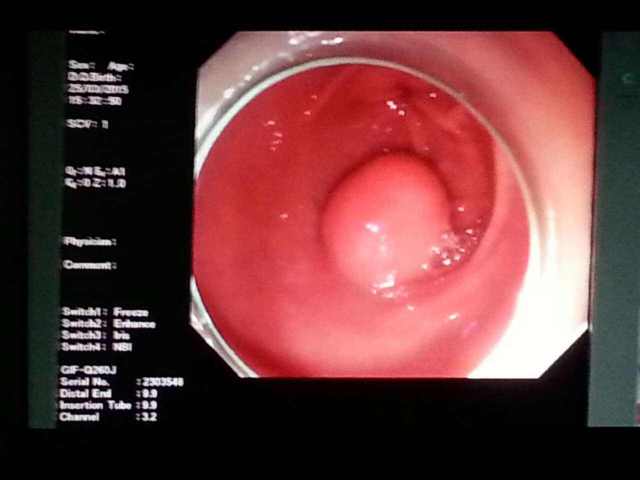

多囊AMH是偏高吗?AMH检查意义在哪?在多囊女生中,AMH往往是偏高的,其原因可能是多囊女生体内的游离睾酮和过量的胰岛素会刺激卵泡分泌AMH,而AMH越高,卵泡数量越多,促卵泡生成素(FSH)就会越低,直接的结果就是导致卵泡无法发育成熟。 判断多囊的指标会是什么呢?可以怎么做检查吗? AMH可以直接反映卵巢储备...